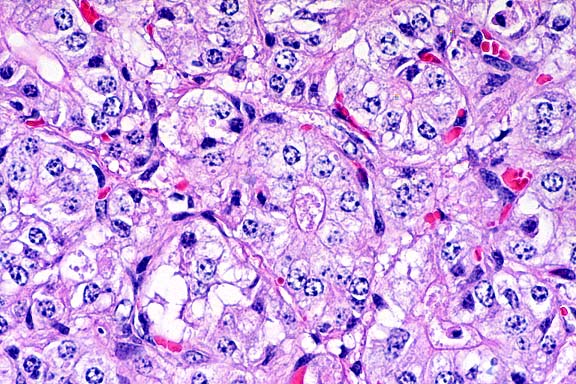

10x

obj

- Case14-4. Heart. There are multiple coalescing foci

of myocardial cell degeneration, necrosis, edema, and an inflammatory

cell infiltrate.

40x

- Case14-4. Heart. This focus of necrosis has loss of

cross striations, hyalinization, and fragmentation of cardiomyocytes,

edema, with karyorrhectic nuclei and scattered macrophages. There

are two clusters of 2-3u diameter protozoa.